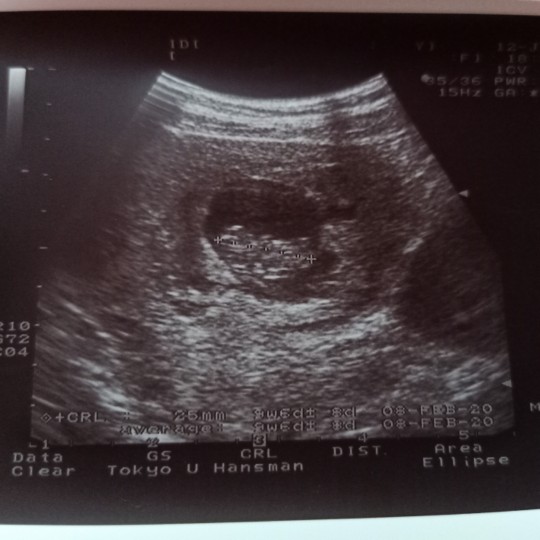

ตอน 8 สัปดาห์คะ